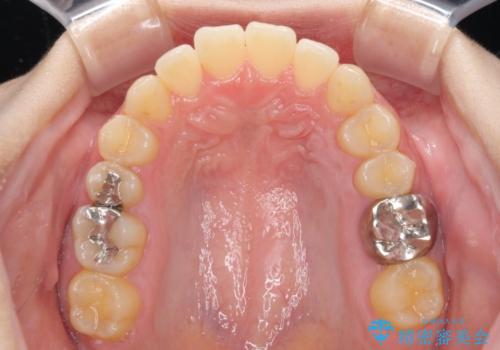

海外勤務中のインビザラインによる矯正治療

- 前歯のクロスバイトを気にして来院され患者様です。

治療期間が世界的な感染症の流行時期と重なったため、海外と日本での往来が困難となり、治療継続が懸念されました。

それでも、しっかりとマウスピースを装着してくださったので、大きなトラブルもなく治療を終えることができました。